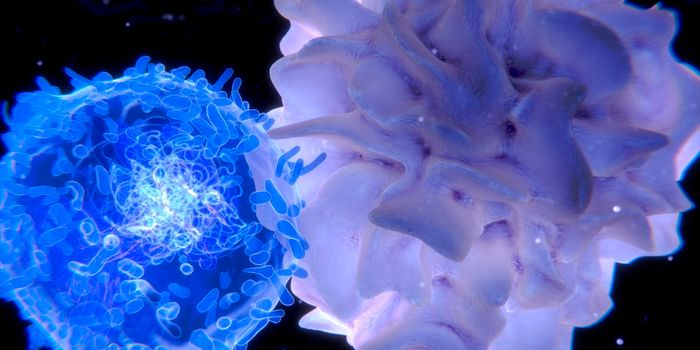

NOV 29, 2023CancerThe CAR-T Revolution: Developing T Cells into Cancer Assassins Cancer has long been a formidable foe, but recent ...

OCT 14, 2016ImmunologyEnhancing a cancer patient’s own T cells to reduce tumor growth is an up-and-coming cancer therapy that is being u ...